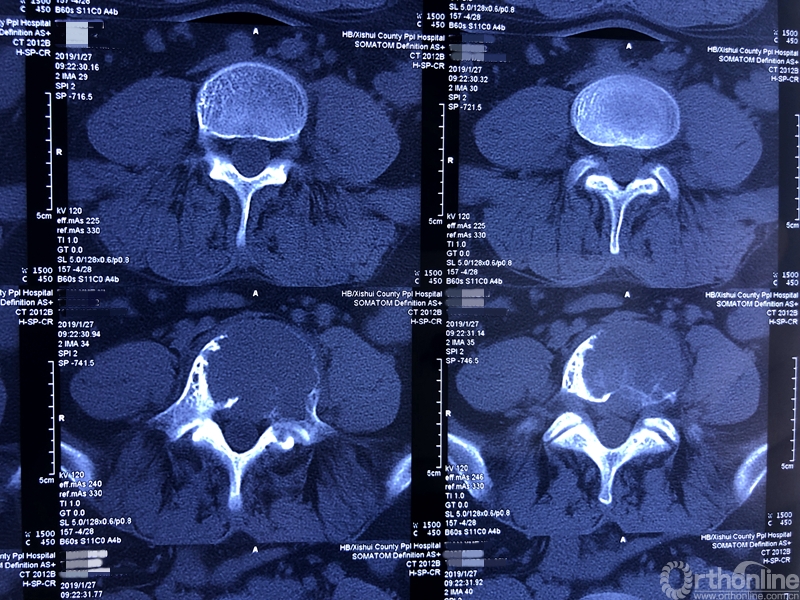

就诊前CT

通过对患者详细的身体检查、穿刺活检和综合评估后,确诊患者是腰椎骨巨细胞瘤,第五腰椎破坏70%以上,邻近软组织也有破坏。这种肿瘤属于交界性的有恶性倾向的良性肿瘤,若不彻底切除,患者疼痛会逐渐加剧,甚至因骨质坍塌而瘫痪,若肿瘤细胞转移更会危及生命。若是能在早期尽快彻底、完全地切除肿瘤及被侵蚀椎体,病人才很可能完全战胜肿瘤。

术前CT三维重建